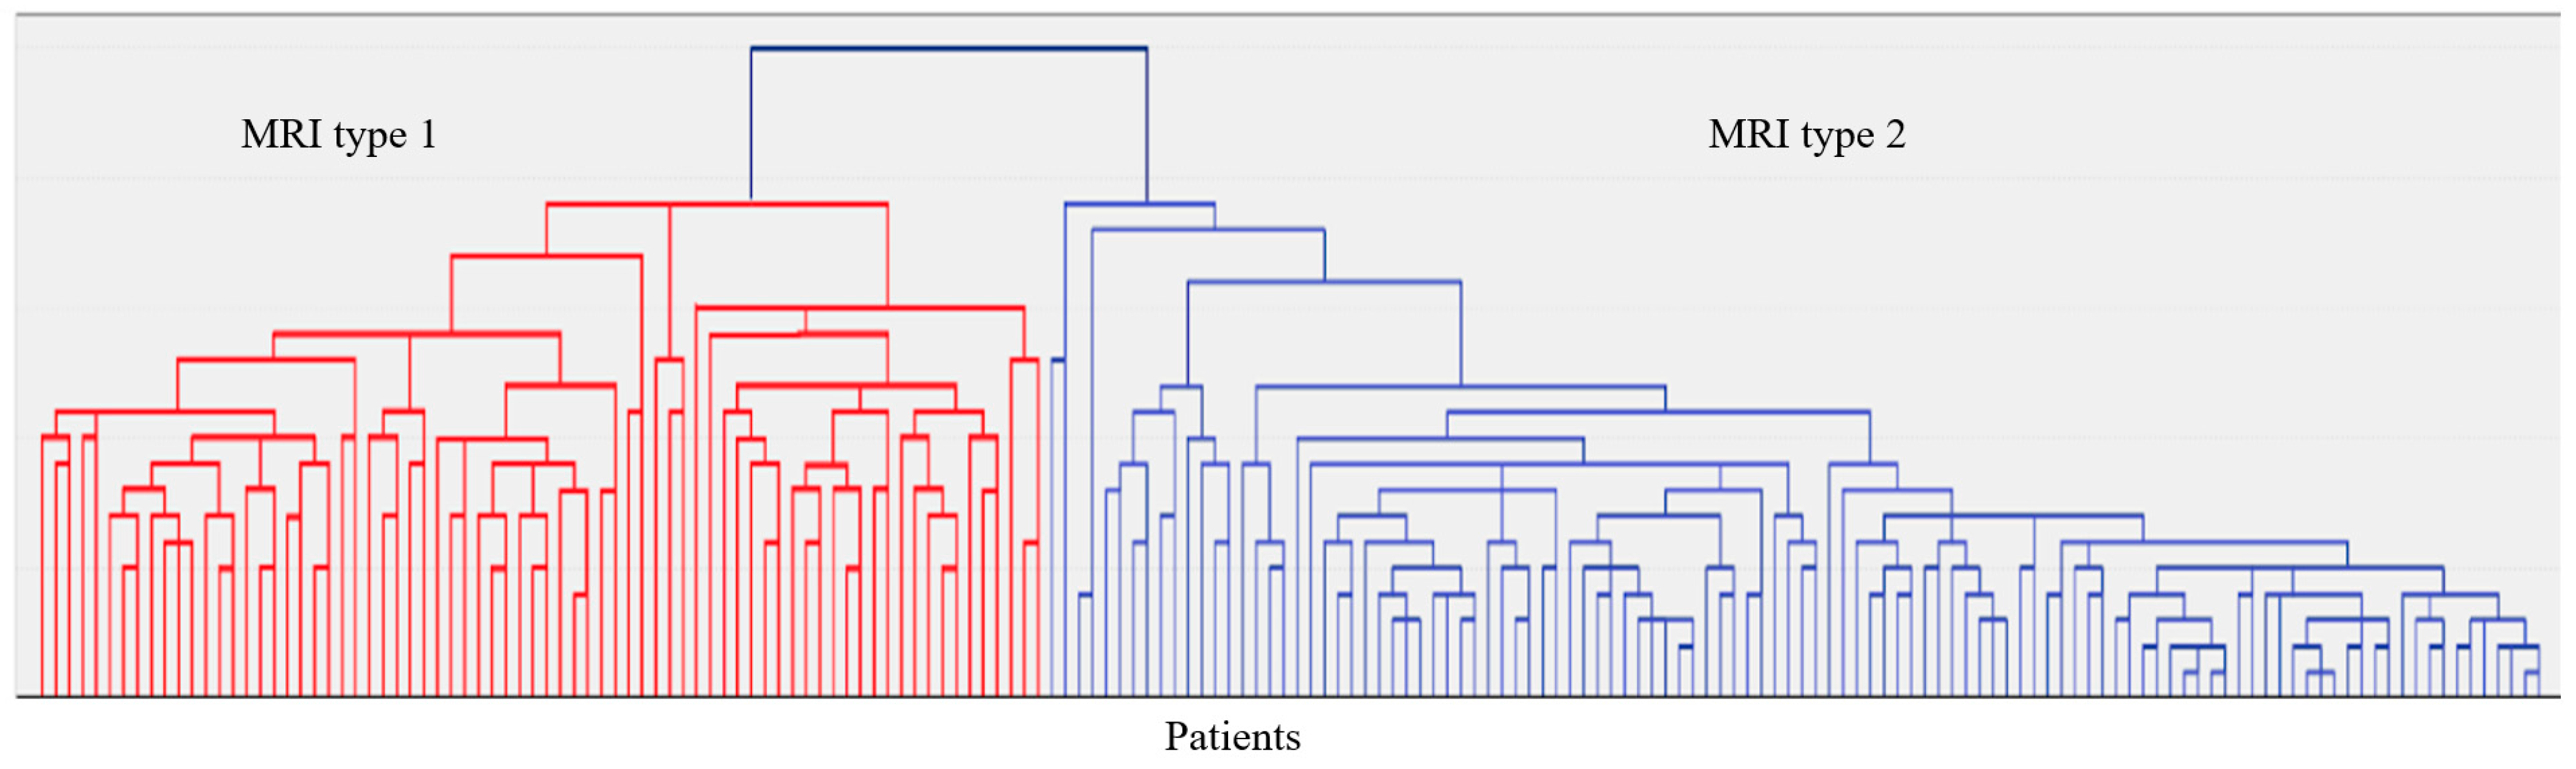

2.1. Clinical and Neuroimaging Characteristics of Two MRI Types of CSVD

| F3 MRI Type 1 | F3 MRI Type 2 |

| WMH: more pronounced in the periventricular and deep regions of the cerebral hemispheres, subcortical structures, external capsule, brainstem, and cerebellum | WMH: periventricular—in the posterior cerebral hemispheres, deep—in the frontal and parietal lobes |

| Lacunes: multiple in subcortical structures and cerebral white matter | Lacunes: single in the white matter of the cerebral hemispheres |

| CMB: juxtacortical CMHs in all regions of the cerebral hemispheres, in subcortical structures | CMB: single juxtacortical CMHs in the white matter of the temporal and parietal lobes |

| Cerebral atrophy: more pronounced | Cerebral atrophy: less pronounced |

| Enlarged PVS: pronounced in subcortical structures | Enlarged PVS: extended |

| Cognitive impairment: more pronounced (MCI and dementia) | Cognitive impairment: less pronounced (SubCI and MCI) |

| Gait disorders: more pronounced | Gait disorders: less pronounced |

| Reduced VEGF-A | Increased TNF-α |